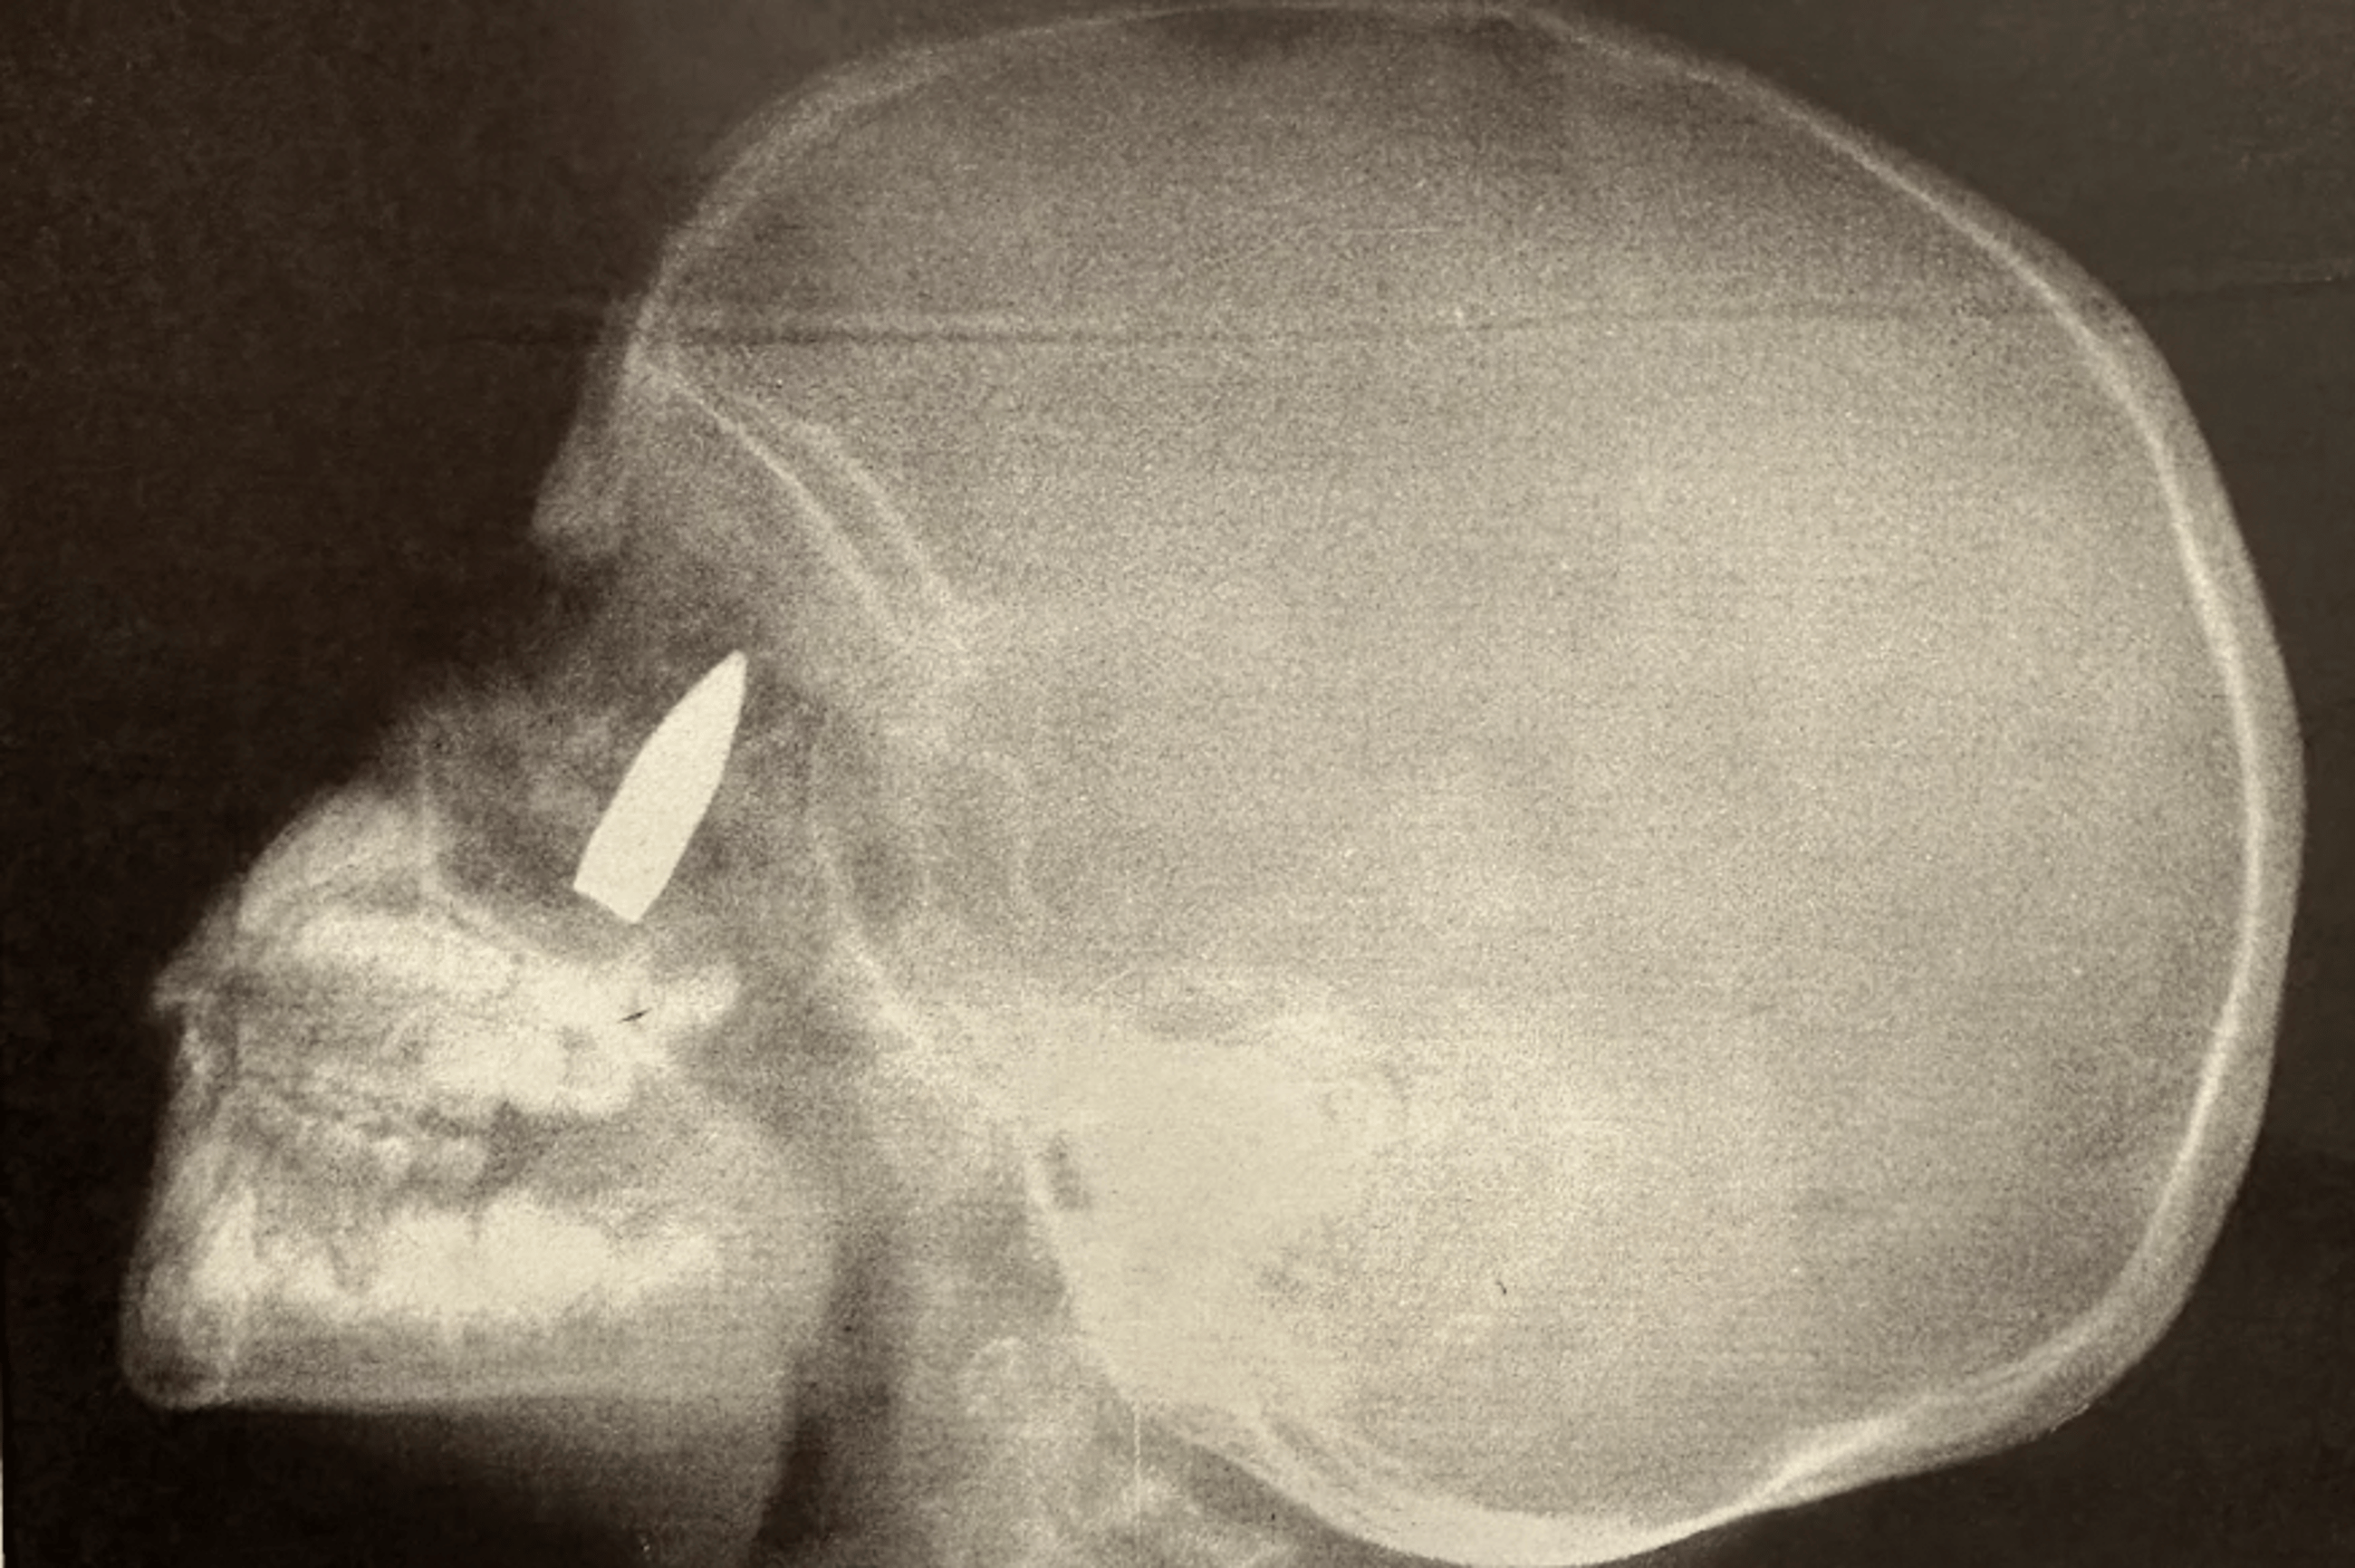

Memorable images from the Medical Post over the years